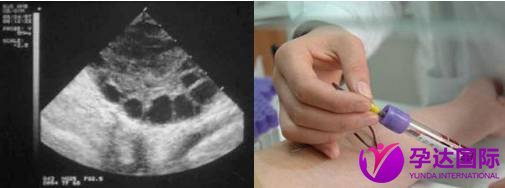

这个过程需要定期到医院通过超声监测和激素抽血以确定何时卵泡成熟。

5、取卵取精:

取卵手术时间并不长,只有十分钟左右,医生通过B超引导,将成熟的卵泡从卵巢内取出。术前会使用止痛药或者麻醉药。